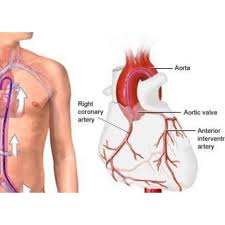

Overview

Package includes:

Days in hospital : 7 to 8 Days (For patient and one attendant)

Days in hotel : 12 Days (For patient and one attendant)

Room type in hospital : Shared

Room type in hotel : Private

Hotel category: Standard

Value added benefits of the CABG:

Ø Doctor consultation charges

Ø Lab tests and diagnostic charges

Ø Room charges inside hospital during the procedure

Ø Surgeon Fee

Ø Nursing charges

Ø Hospital surgery suite charges

Ø Anesthesia charges

Ø Routine medicines and routine consumables (bandages, dressings etc.)

Ø Food and Beverages inside hospital stay for patient and one attendant.

Extra benefits:

Overview

Package includes:

Days in hospital : 7 to 8 Days (For patient and one attendant)

Days in hotel : 14 Days (For patient and one attendant)

Room type in hospital : Shared

Room type in hotel : Private

Hotel category: Standard

Value added benefits of the CABG and AVR:

Overview

Package includes:

Days in hospital : 7 to 8 Days (For patient and one attendant)

Days in hotel : 14 Days (For patient and one attendant)

Room type in hospital : Shared

Room type in hotel : Private

Hotel category: Standard

Value added benefits of the CABG and MVR: